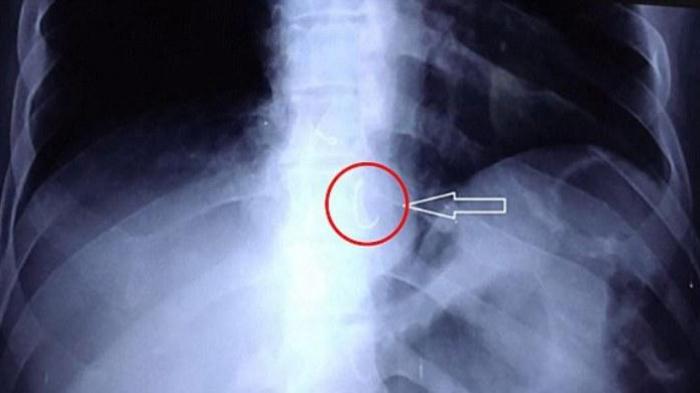

Namun, setelah itu ia batuk-batuk selama dua hari, mengalami sesak di dada, dan sulit menelan saat makan. Saat menjalani pemeriksaan di rumah sakit dengan sinar X, ternyata ada gigi palsu yang telah bergeser sejauh sekitar 32 cm dari mulutnya atau tepatnya ada di kerongkongannya.

Menurut kasus yang di laporkan di BMJ case, tim dokter kemudian berusaha mengambil gigi palsu tersebut dengan menggunakan alat yang dimasukkan ke kerongkongan. Namun, ada dinding kerongkongan yang menghalangi, sehingga sulit mengangkat gigi palsu tersebut.